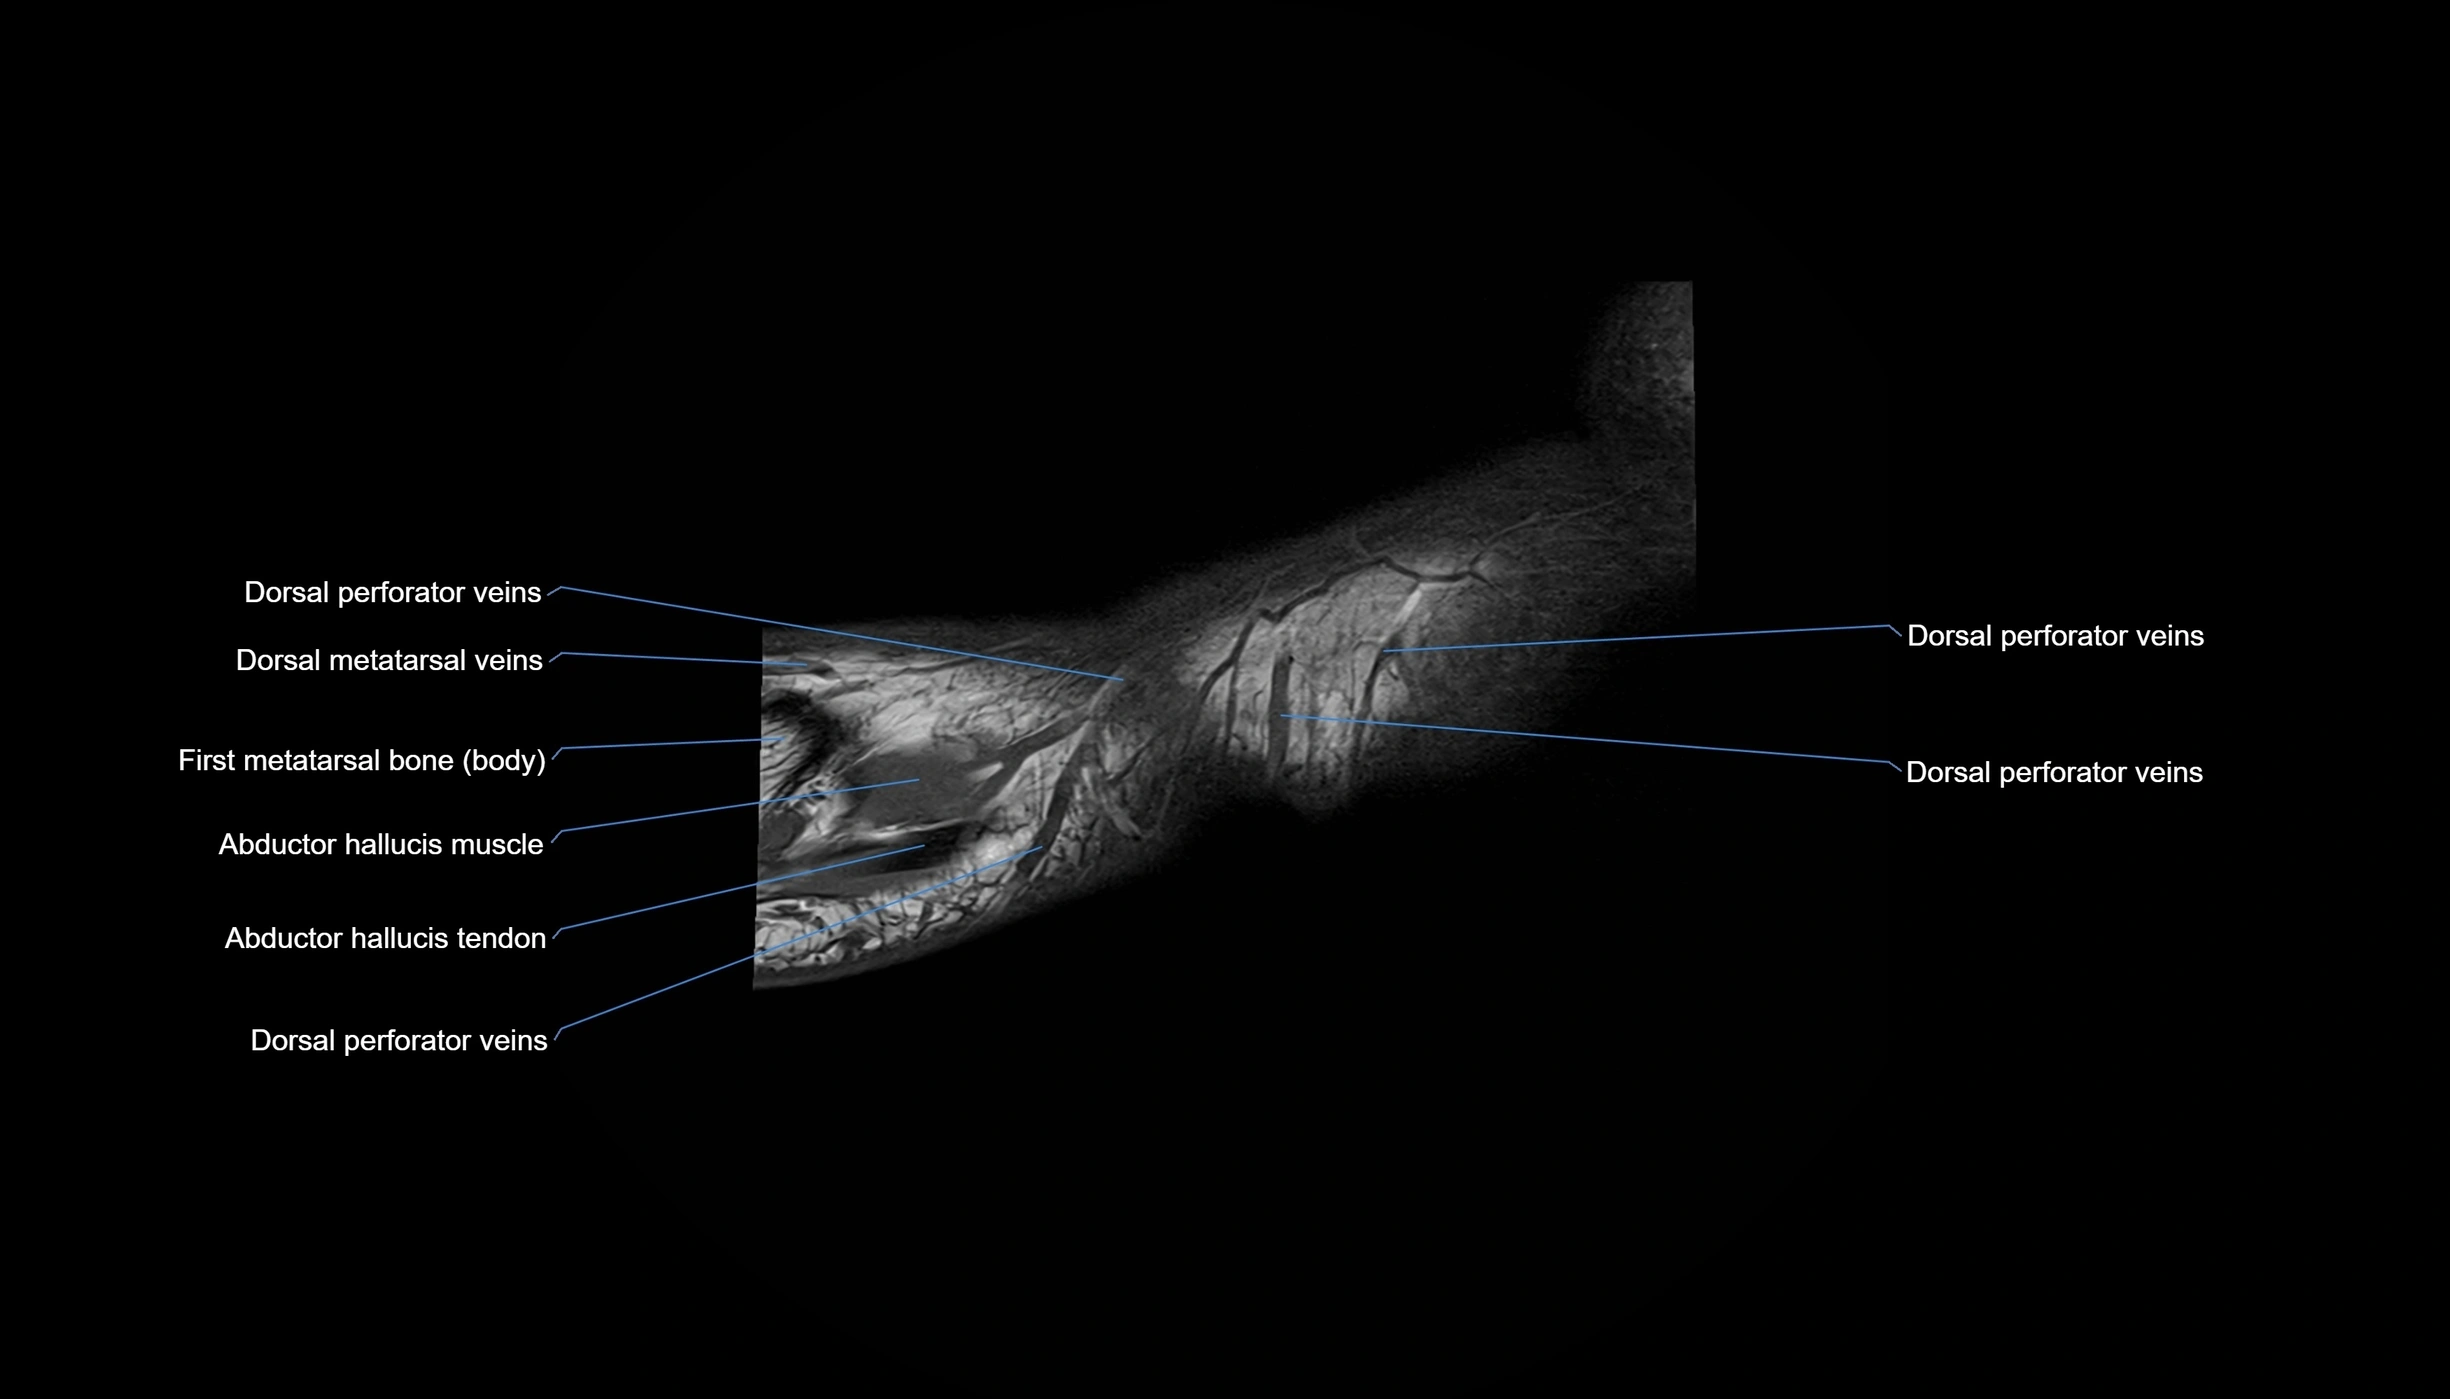

MRI image